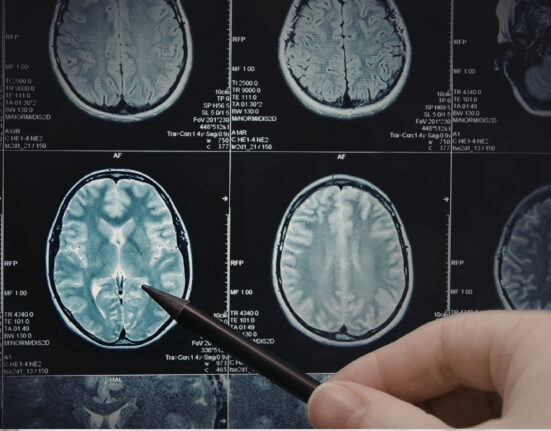

Iubirea, explicată de Dragobete din perspectiva psihiatriei: ce se întâmplă în creier când ne îndrăgostim

Astăzi, 24 februarie, când în tradiția românească se sărbătorește Dragobetele, vorbim despre „fluturii din stomac” și din perspectivă medicală. Iubirea.